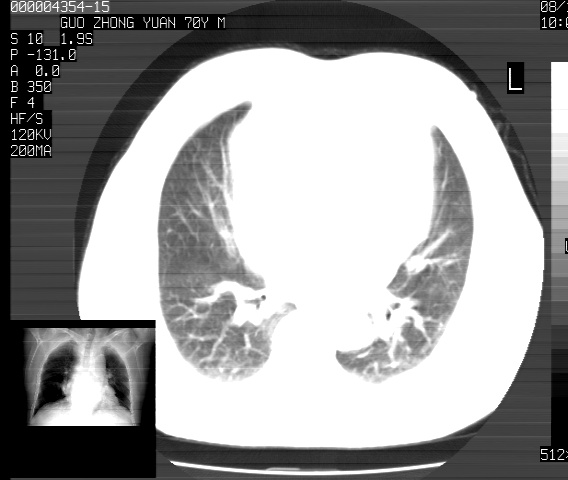

以下是引用sdzyy在2008-12-1 11:49:00的发言:[br]图像不全,请上传,右下肺炎症可能性大,占位待排.

以下是引用zjzjr在2008-12-1 14:53:00的发言:[br]图像不全,请上传,右下肺炎症可能性大,占位待排.心影增大,建议进一步检查.